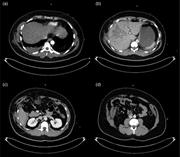

Caecum herniation through the Foramen of Winslow

Sarah F. Powell-Brett and others

Journal of Surgical Case Reports, Volume 2012, Issue 12, December 2012, rjs016, https://doi.org/10.1093/jscr/rjs016